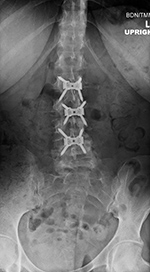

| Zero-Profile lumbar fixation L2-L4 |

| 45 year-old woman with L2-5 anterior lumbar interbody fusion (ALIF) for low back pain. |